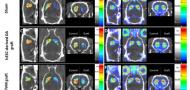

Paisey, S.J., Jones, L.R., Harrison, D.J., Drummond, N.J., Edwards, O.Z., Canham, M.A., Roberton, V.H., Marshall, C., Parker, G., Hills, R., et al. (Neurobiology of Disease, June 2025)